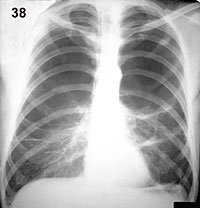

Esquema 38 Comentario placa 38 La hipertranslucencia de los lóbulos superiores es extrema, con carencia total de vasos. La alteración se encuentra limitada en su parte inferior por imágenes lineales arciformes que corresponden a parte de las paredes de grandes bulas bilaterales. |